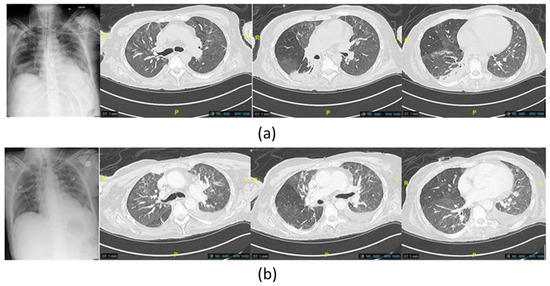

Figure 4. (a) Imaging chest X-ray and computed tomography scan of the last P. aeruginosa lung infection, showing new appeared posterior consolidations of the basal right lung before the administration of phage therapy (b) and at the end of the treatment, showing improvement in the posterior region of the right lung.